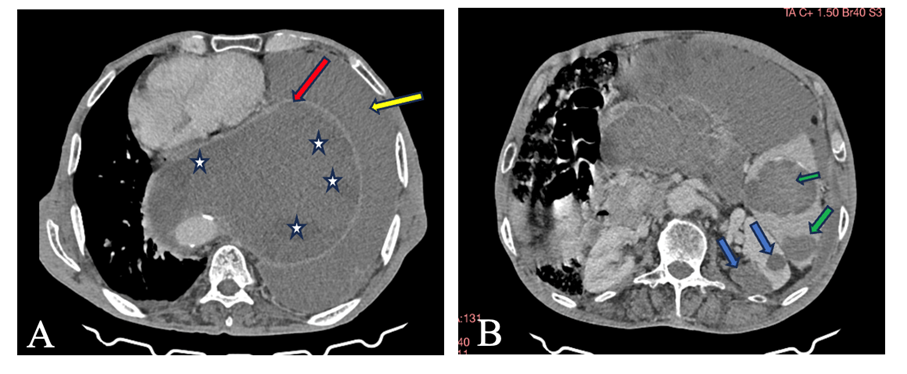

- CT imaging revealed multiple well-defined cystic formations with thin, regular walls and heterogeneous internal content, consistent with hydatid cysts. Several cysts showed areas of varying density, corresponding to daughter vesicles and detached membranes, producing the characteristic “water-lily” and “rosette” appearances. These lesions were distributed in the mediastinum, peritoneal cavity, spleen, and both kidneys, causing mass effect on adjacent structures without signs of invasion. Some cysts demonstrated calcified walls, suggesting chronic evolution, while others retained a typical fluid density, indicating different stages of disease activity.

Figure A: Axial CT scan with contrast injection, large cystic posterior mediastinal mass (red arrow) with areas of variable density (daughter cysts) (white stars).

Large left pleural effusion (yellow arrow).

Figure B: Axial CT scan with contrast injection, cystic formations with the same characteristics in the spleen (green arrows) and left kidney (blue arrows).